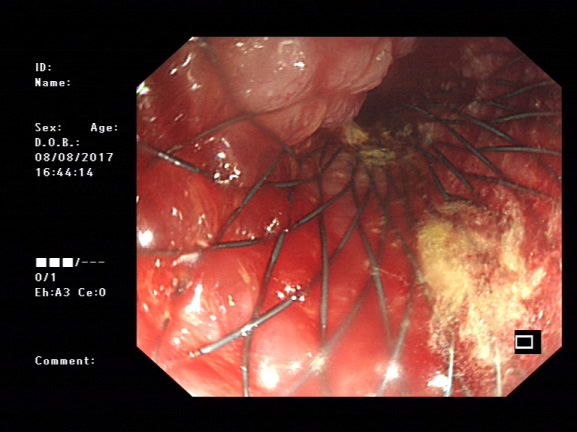

Colonoscopy was performed. The colon became too narrow to pass the scope at 30cms from the anus. Erosive haemorrhagic mucosa was seen and colon cancer was diagnosed. To relieve its obstruction, a stent (80x25mm) was implanted into the narrow lumen. Liquids were then passed through the stent, indicating the obstruction was resolved (Figure 2). One week late, the patient’s general condition became much better and colectomy was performed (Figure 3). The segment with cancer was removed and the patient gained full recovery without complication (Figure 4) and was discharged within one week after colectomy.

Figure 2 Left: sigmoidal colon lesion before inserting stent. Right: after insertion of stent. Liquids were then passed through the stent, indicating the obstruction was resolved.